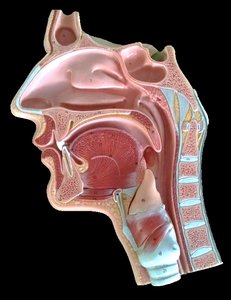

Nasal Cavity and Pharynx

Nasal Vestibule: The anterior part of the nasal cavity, just inside the nostrils.

Hard Palate: The bony anterior portion of the roof of the mouth, separating the nasal and oral cavities.

Soft Palate: The muscular posterior portion of the roof of the mouth.

Pharynx: A muscular tube that serves as a passageway for both air and food; divided into nasopharynx, oropharynx, and laryngopharynx.

Uvula: A small projection from the posterior edge of the soft palate.

Regions of the Pharynx

Nasopharynx: Superior portion, behind the nasal cavity.

Oropharynx: Middle portion, behind the oral cavity.

Laryngopharynx: Inferior portion, leading to the larynx and esophagus.

Larynx and Tracheal Cartilages

Major Cartilages and Ligaments

Hyoid Bone: U-shaped bone above the larynx, supports the tongue.

Thyroid Cartilage: Largest laryngeal cartilage, forms the Adam's apple.

Cricoid Cartilage: Ring-shaped cartilage below the thyroid cartilage.

Epiglottis: Leaf-shaped cartilage that covers the laryngeal inlet during swallowing.

Tracheal Cartilages: C-shaped rings that keep the trachea open.

Ligaments: Hyo-thyroid, thyro-cricoid, and crico-tracheal ligaments connect the cartilages.